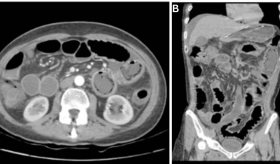

De acuerdo con el portal Mayo Clinic, el cáncer de esófago se refiere a la proliferación anormal de células en el esófago, un conducto largo y hueco que conecta la garganta con el estómago, facilitando el paso de los alimentos. Este tipo de cáncer generalmente comienza en las células que recubren el interior del esófago, aunque puede desarrollarse en cualquier parte del mismo. Es más común en los hombres y el consumo de alcohol y tabaco son factores de riesgo conocidos.

El tratamiento para el cáncer de esófago suele implicar una intervención quirúrgica para extirpar el tumor. Además, pueden emplearse otros tratamientos como la quimioterapia, la radioterapia o una combinación de ambos. En algunos casos, se recurren a terapias dirigidas o a la inmunoterapia.

El cáncer de esófago puede no presentar síntomas en sus primeras etapas. Los signos de la enfermedad suelen aparecer cuando ya está avanzada.

Algunos de los síntomas comunes del cáncer de esófago incluyen: